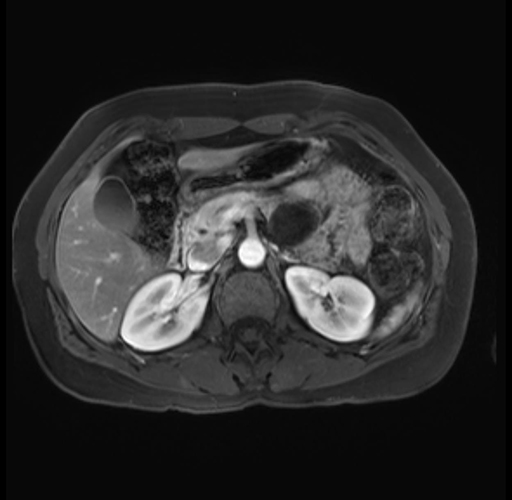

Imaging Analysis

Look through the patient's CT scan to identify any areas of concern for the necessary procedure.

Based on your CT findings, which issue(s) are present and would give reason for "planned slowing down moment(s)" in this case?

Considering a standard distal pancreatectomy procedure, what step(s) of the operation would you do differently in this case?